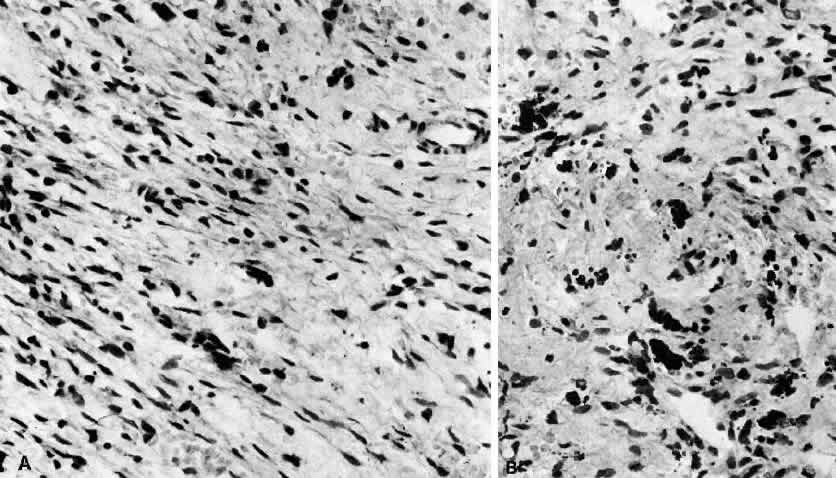

Nodular or pseudosarcomatous fasciitis, while not usually considered part of the spectrum of idiopathic orbital inflammation, represents a localized inflammatory disease of idiopathic origin. It appears to be a reactive process involving a proliferation of immature connective tissue elements along with acute and chronic inflammatory foci (Fig. 7).102–106 This entity has been reported periorbitally in the eyelid as well as in the epibulbar tissue. It may also occur in the anterior or deep orbit. It appears as a rapidly growing mass arising over several weeks or months. It may or may not be associated with pain. At surgery, the lesion appears fairly well demarcated and slightly reddish.

Fig. 7. Fasciitis. A. “Pseudosarcomatous” reactive inflammatory condition is composed predominantly of a loose arrangement of fibroblasts with scattered chronic inflammatory cells (H&E, ×240). B. Conspicuous hemosiderin-laden macrophages are seen in center of photomicrograph. The presence of abundant numbers of capillaries in the inflammatory tissue results in hemorrhage and the presence of blood breakdown products (H&E, ×240).

Microscopically there is a proliferation of immature and active-appearing fibroblasts within the orbital fascial planes.102–106 These fibroblasts may be loosely connected with occasional myxoid foci interposed. Slits often appear between the fibroblasts, which appear to be quite plump and have basophilic cytoplasm. There may be rare mitoses among these cells. Only a minimal amount of collagen deposition is present. The appearance of a gradient from immature fibroblastic elements to more mature fibroblasts is characteristic of this lesion. Also associated with this process is acute and chronic inflammatory cells, capillary and endothelial cell proliferation, and occasional giant cells. Occasionally elements of this inflammatory process can be seen to invade surrounding muscle fibers and orbital fat. The proliferating capillaries are friable and bleed. When this occurs, hemosiderin-laden macrophages can be identified in the tissue. Electron microscopic evaluation of the cells present in this process shows that most are myofibroblasts. These are cells containing rough endoplasmic reticulum and no basement membrane like fibroblasts but also cytoplasmic actin filaments with fusiform densities like smooth muscle cells.3